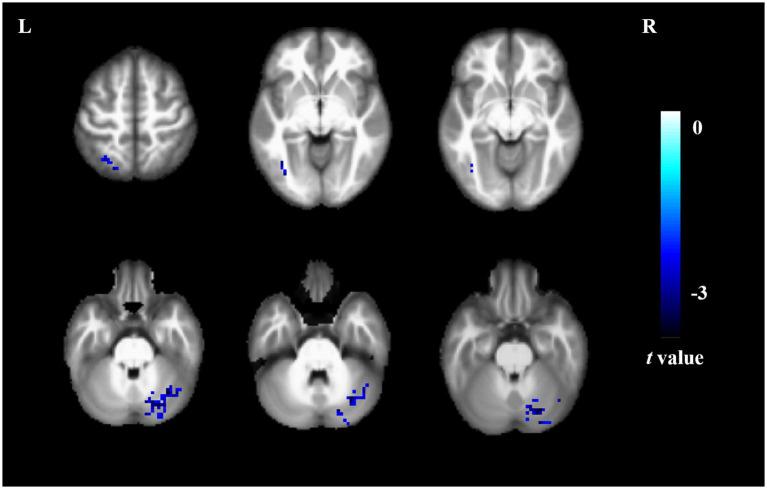

Short sleep duration group showed significantly increased ALFF value in the bilateral middle frontal gyrus and right insula; significantly increased ReHo value in the left superior parietal gyrus, and decreased ReHo value in the right crebellum; significantly decreased DC value in the left inferior occipital gyrus, left superior parietal gyrus and right cerebellum ( < 0.05, AlphaSim correction). The ALFF value of right insula is significantly associated with symbol digit modalities test (SDMT) score ( = -0.363,  = 0.033).

短睡眠时间组双侧额中回和右侧岛叶的ALFF值显著升高;左侧顶上小叶的ReHo值显著升高,右侧小脑的ReHo值降低;左侧枕下回、左侧顶上小叶和右侧小脑的DC值显著降低(P<0.05,AlphaSim校正)。右侧岛叶的ALFF值与符号数字模式测验(SDMT)得分显著相关(r=-0.363,P=0.033)。